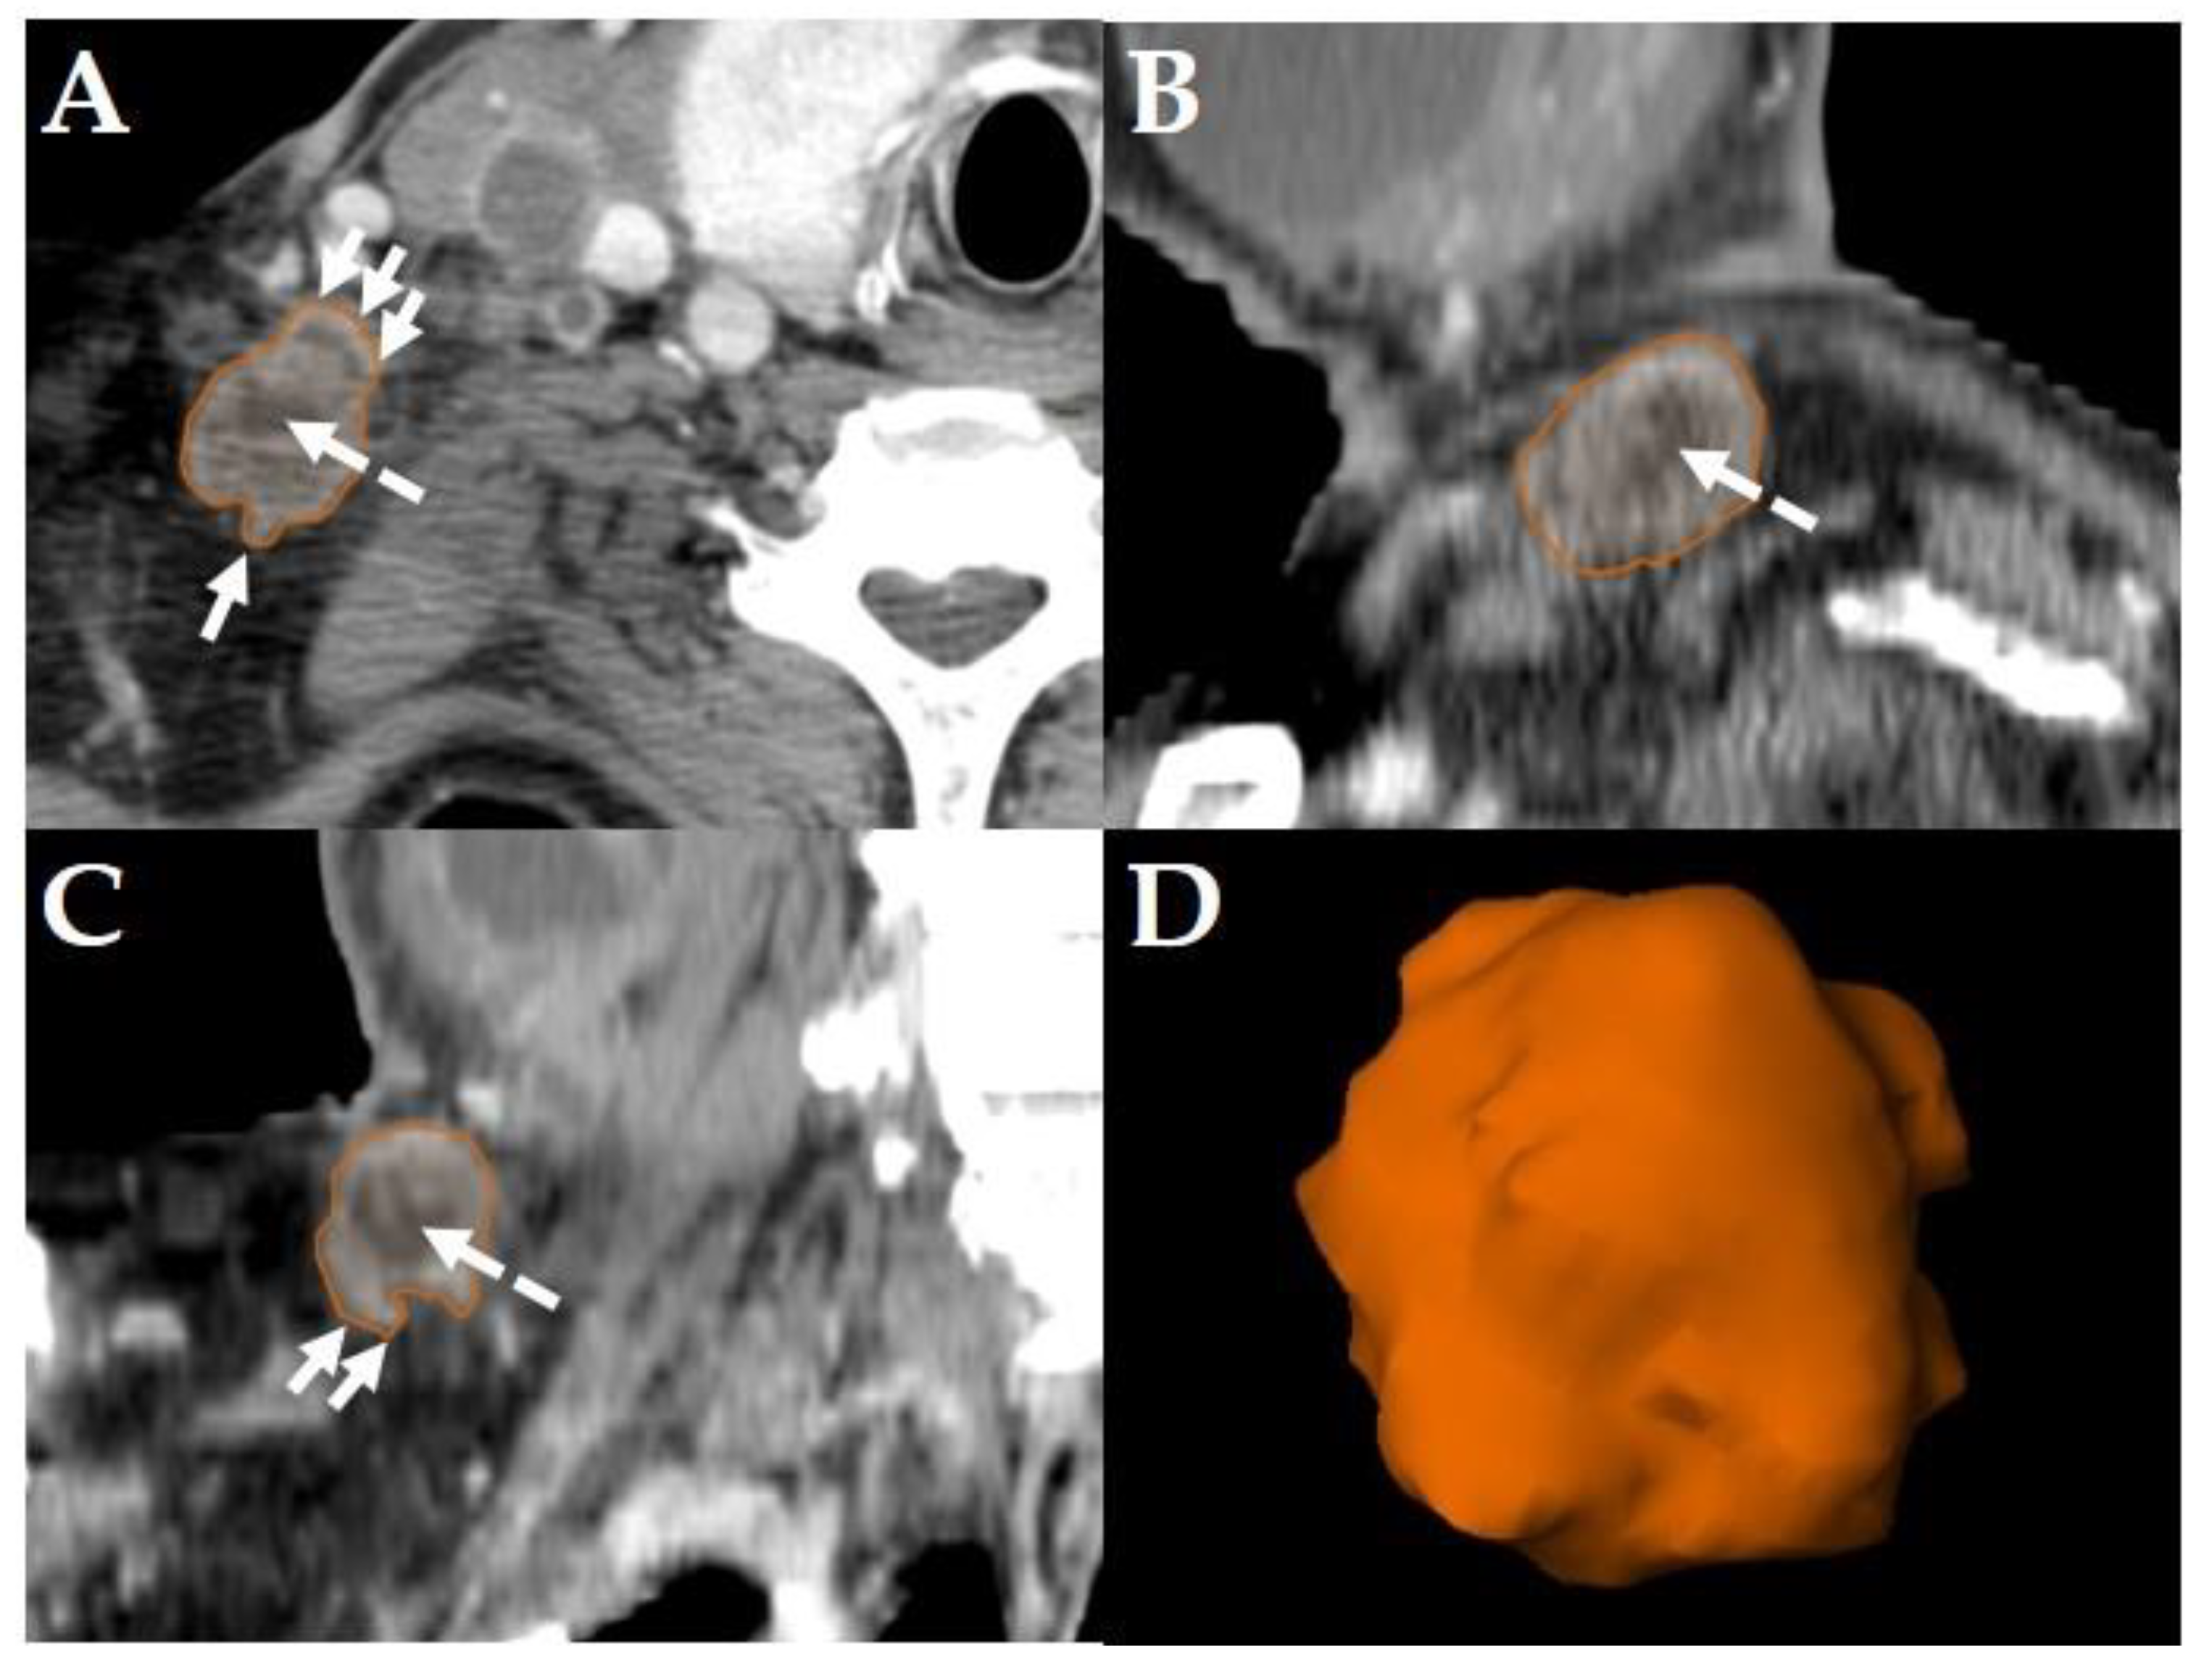

All diagnostic-, planning- and restaging-CTs were imported to the segmentation software (Elements, BrainLab, Munich, Germany). For each patient the three largest LNs were manually segmented in all data sets slice-by-slice in the axial plane using the “paint on slices” tool provided by the software. All segmented LNs were examined by two experienced, board certified head and neck radiologists with more than 15 years of clinical experience in head and neck CT reporting. The segmented LNs were classified as “pathologic” (Figure 2), “pathologic with ECS” (Figure 3) or “non-pathologic” (Figure 4), complying with current CT reading criteria for LN-malignancy [5,6,7].

Figure 3. Example of a LN classified as “pathologic with ECS” in a Staging-CT of a 53-year-old, male HNSCC-patient of the oral cavity staged cT2 cN3b cM0. Manual segmentation in the axial plane (A); sagittal (B), coronal (C) reformatted views and three-dimensional rendering (D) of the LN are provided by the software. Solid arrows show soft tissue infiltration and an irregular LN capsule. Dashed arrows show central necrosis.

LNs were classified “pathologic with ECS” if in staging-, planning- or restaging-CTs, in addition to the criteria mentioned above [5,6], apparent fat/soft-tissue infiltration, infiltration of the sternocleidomastoid muscle, the internal jugular vein, or the carotid artery was observed [7]. Consequently, all LNs classified as “pathologic with ECS” were considered “pathologic”, too, but not all “pathologic” LNs were classified “pathologic with ECS” (Figure 3).

Consequently, the classification of the segmented LNs in “pathologic” (Figure 2), “pathologic with ECS” (Figure 3) and “non-pathologic” (Figure 4) by the two experienced head-and-neck-radiologists based on established criteria [5,6,7] was defined as reference.